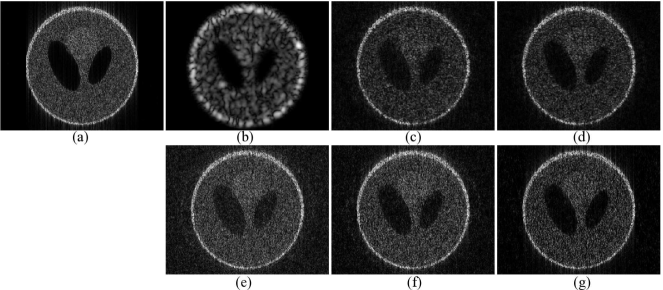

Appendix C Comparison with the compressive deconvolution method in [26]

In this appendix we show an experiment aiming to evaluate the performance of the proposed approach compared to the one in [26], denoted by  CD_Amizic herein. The comparison results are obtained on the standard 256×256256256256\times 256 Shepp-Logan phantom. The measurements have been generated in a similar manner as in [26], i.e. the original image was normalized, degraded by a 2D2𝐷2D Gaussian PSF with a 5-pixel variance, projected onto a structured random matrix (SRM) to generate the CS measurements and corrupted by an additive Gaussian noise. We should remark that in [26] the compressed measurements were originally generated using a Gaussian random matrix. However, we have found that the reconstruction results with CD_Amizic are slightly better when using a SRM compared to the PSNR results reported in [26]. Both methods were based on the generalized TV to model the image to be estimated and the 3-level Haar wavelet transform as sparsifying basis ΨΨ\Psi. With our method, the hyperparameters were set to {α,μ,β}={101,105,102}𝛼𝜇𝛽superscript101superscript105superscript102\{\alpha,\mu,\beta\}=\{10^{-1},10^{-5},10^{2}\}. The same hyperparameters as reported in [26] were used for CD_Amizic. Both algorithms based on the non-blind deconvolution (PSF is supposed to be known) and used the same stopping criteria.

Fig.7 shows the original Shepp-Logan image, its blurred version and a series of compressive deconvolution reconstructions using both our method and CD_Amizic for CS ratios running from 0.40.40.4 to 0.80.80.8 and a SNR of 404040 dB. Table.IV regroups the PSNRs obtained with our method and with CD_Amizic for two SNRs and for four CS ratios from 0.20.20.2 to 0.40.40.4. In each case, the reported PSNRs are the mean values of 101010 experiments. We may observe that our method outperforms CD_Amizic in all the cases, allowing a PSNR improvement in the range of 0.50.50.5 to 222 dB. Moreover, Fig.8 shows the computational times with CD_Amizic and the proposed method, obtained with Matlab implementations (for CD_Amizic, the original code provided by the authors of [26] has been employed on a standard desktop computer (Intel Xeon CPU E5620 @ 2.40GHz, 4.00G RAM). We notice that our approach is less time consuming than CD_Amizic for all the CS ratios considered.

Refer to caption

Figure 7: Shepp-logan image and its compressive deconvolution results for a SNR of 40dB. (a) Original image, (e) Blurred image, (b,c,d) Compressive deconvolution results with CD_Amizic for CS ratios of 0.8, 0.6 and 0.4, (f,g,h) Compressive deconvolution results with the proposed method for CS ratios of 0.8, 0.6 and 0.4.

TABLE IV: PSNR assessment for Shepp-Logan phantom

SNR CS ratios 20% 40% 60% 80%

40dB CD_Amizic 23.04 24.88 25.30 25.51

Proposed method 24.09 25.38 26.26 26.91

30dB CD_Amizic 22.61 24.05 24.40 24.55

Proposed method 23.92 25.12 25.82 26.33